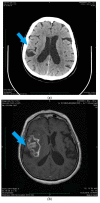

Malignant glioma is a brain tumor with a very high mortality rate resulting from the specific morphology of its infiltrative growth and poor early detection rates. The causes of one of its very specific types, i.e., post-traumatic glioma, have been discussed for many years, with some studies providing evidence for mechanisms where the reaction to an injury may in some cases lead to the onset of carcinogenesis in the brain. In this review of the available literature, we discuss the consequences of breaking the blood⁻brain barrier and consequences of the influx of immune-system cells to the site of injury. We also analyze the influence of inflammatory mediators on the expression of genes controlling the process of apoptosis and the effect of chemical mutagenic factors on glial cells in the brain. We present the results of experimental studies indicating a relationship between injury and glioma development. However, epidemiological studies on post-traumatic glioma, of which only a few confirm the conclusions of experimental research, indicate that any potential relationship between injury and glioma, if any, is indirect.